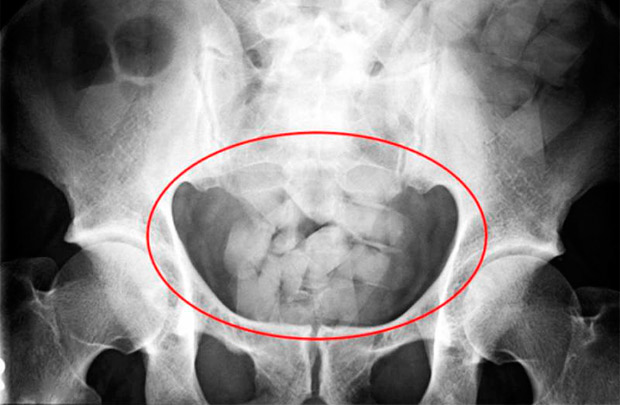

При задержании, пытаясь избежать ответственности, сверток с наркотиком светлогорец проглотил. Пришлось делать промывание желудка.